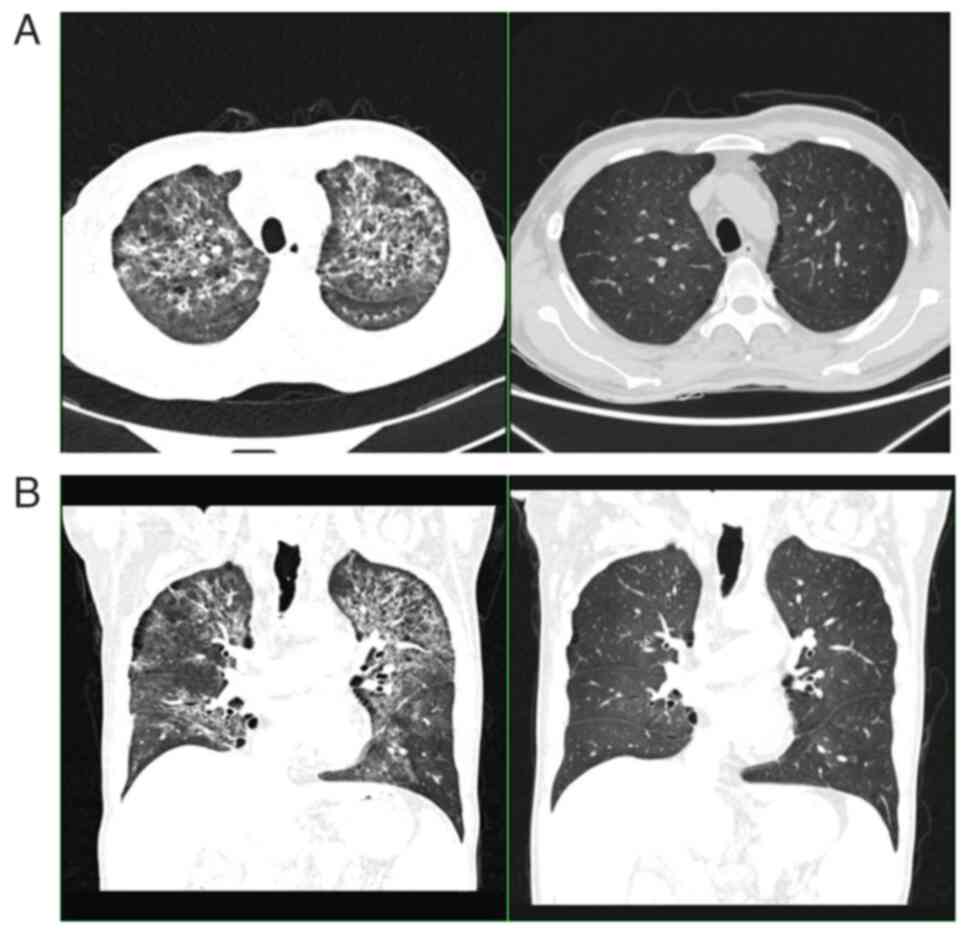

After two courses of chemotherapy, a CT showed that the patient's lymph nodes were smaller than before (Fig. 2). However, the patient appeared to have worsening pruritus. Immunohistochemical examination of the lymph node specimen revealed CD20+, PAX-5+, CD3+, Ki-67+ (20–30%), CD10-, BCL-6+, MUM-1+, PD-1+, CXCL-13-, CD30+, and CD15-; (Fig. 3). T-cell clone analysis was performed using the BIOMED-2 polymerase chain reaction protocol. On molecular examination, TCRβDB+Jβ1/2 showed monoclonal rearrangement and Vβ+Jβ2 showed oligoclonal rearrangement with PTPRD gene mutation. The pathological diagnosis was non-Hodgkin peripheral (mature) T-cell lymphoma, prone to AITL. Thus, the patient was diagnosed with lymphoma, which was a composite of AITL and HL (International Prognostic Index, 3; Prognostic Index for T-cell lymphoma, 2). Given this diagnosis, the patient was scheduled for etoposide, prednisone, vincristine, cyclophosphamide, and doxorubicin (EDOCH). However, the patient died of a lung infection before starting further treatment (Fig. 4).

Figure 4.

CT images of pulmonary infection. (A) Cross section, and (B) coronal planes. The images after two courses of chemotherapy are shown on the right. The patient had a severe pulmonary infection and extensive exudation.